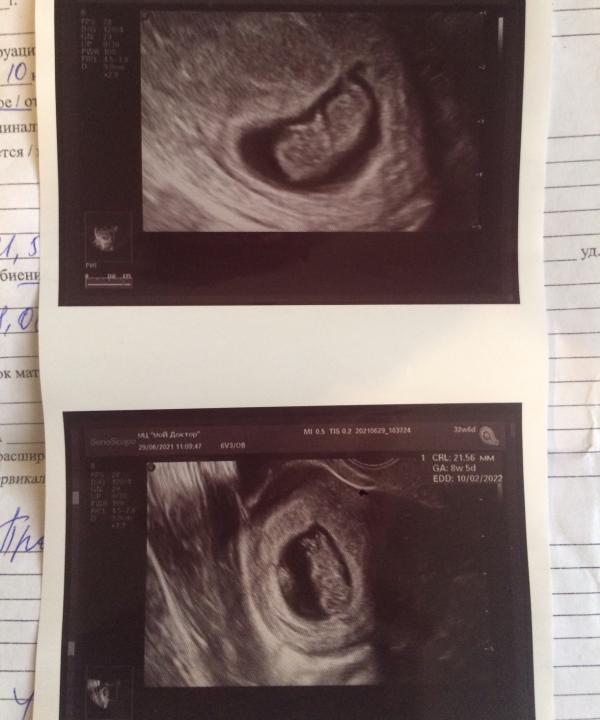

8-9 недель

180 ударов

21мм❤️

Я с нетерпением жду тебя,малыш❤️